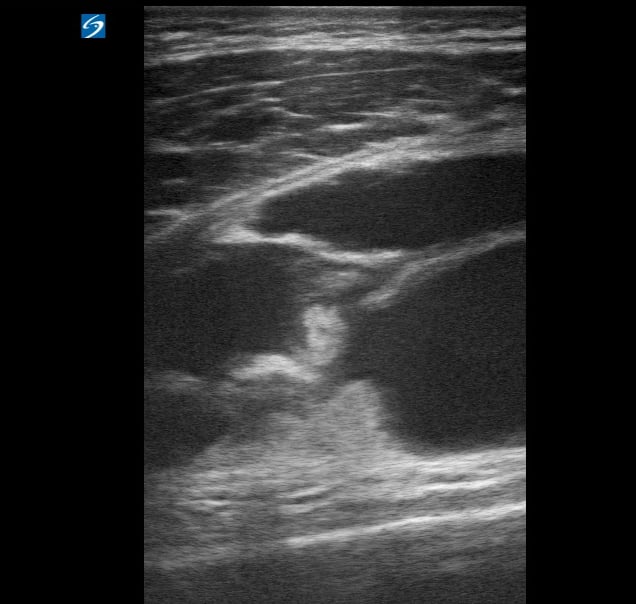

A tendon tear, in musculoskeletal (MSK) ultrasound, refers to a rupture or partial disruption of the fibrous tissue connecting muscle to bone. This common injury can range from minor fraying to a complete tear, significantly impacting joint function and mobility. Ultrasound imaging is invaluable for diagnosing tendon tears, allowing real-time visualization of the tendon’s integrity, tear size, and associated inflammation.

Early and accurate diagnosis via medical ultrasound is crucial for guiding appropriate treatment, whether it’s conservative management or surgical repair. Key ultrasound findings include focal hypoechogenicity, fiber discontinuity, and retraction of the torn ends, providing essential information for patient care and rehabilitation.